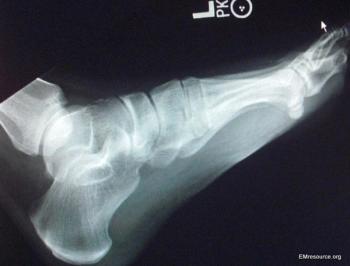

A 32-year-old man arrives at the ED unable to walk after jumping from a wall. This foot injury is often missed on x-ray. Do you see it?

Missed fractures of the foot are not uncommon. Examine the lateral x-ray view of this injury carefully to understand why.